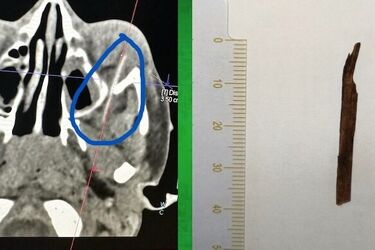

- Chłopiec trafił do Kliniki Okulistyki szpitala dziecięcego z podejrzeniem stanu zapalnego lewego oka. W badaniu klinicznym pacjenta widoczna była tylko niewielka rana spojówki. Dopiero tomografia pokazała, że ciało obce utkwiło w dolnej części oczodołu, dochodząc do szczeliny oczodołowej dolnej. To okolice bardzo ważne dla prawidłowego funkcjonowania oka, czy dla samego procesu widzenia. To obszar funkcjonowania wielu mięśni, nerwów, czy tętnicy ocznej - informuje Medyk Białostocki.

Chłopczyk miał dużo szczęścia. Lekarzom udało się wyjąć z oczodołu drzazgę o długości 5 cm. Wszystko się powiodło, nie zanosi się na to, by z powodu wypadku dziecko miało jakieś problemy zdrowotne.